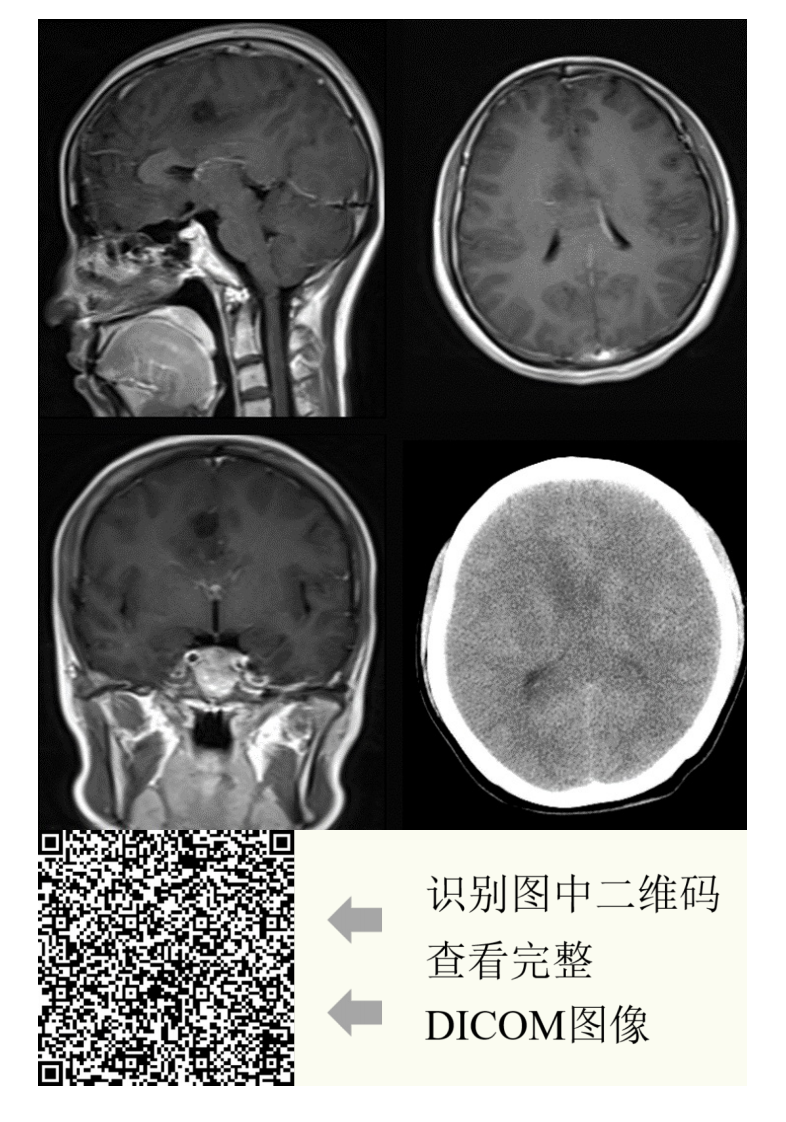

20210608_2【晨读结果公布】2021.06.07神经系统疾病——病例1:间变型少突胶质细胞瘤;病例2:PCNSL;病例3:胼胝体急性梗死.pdf